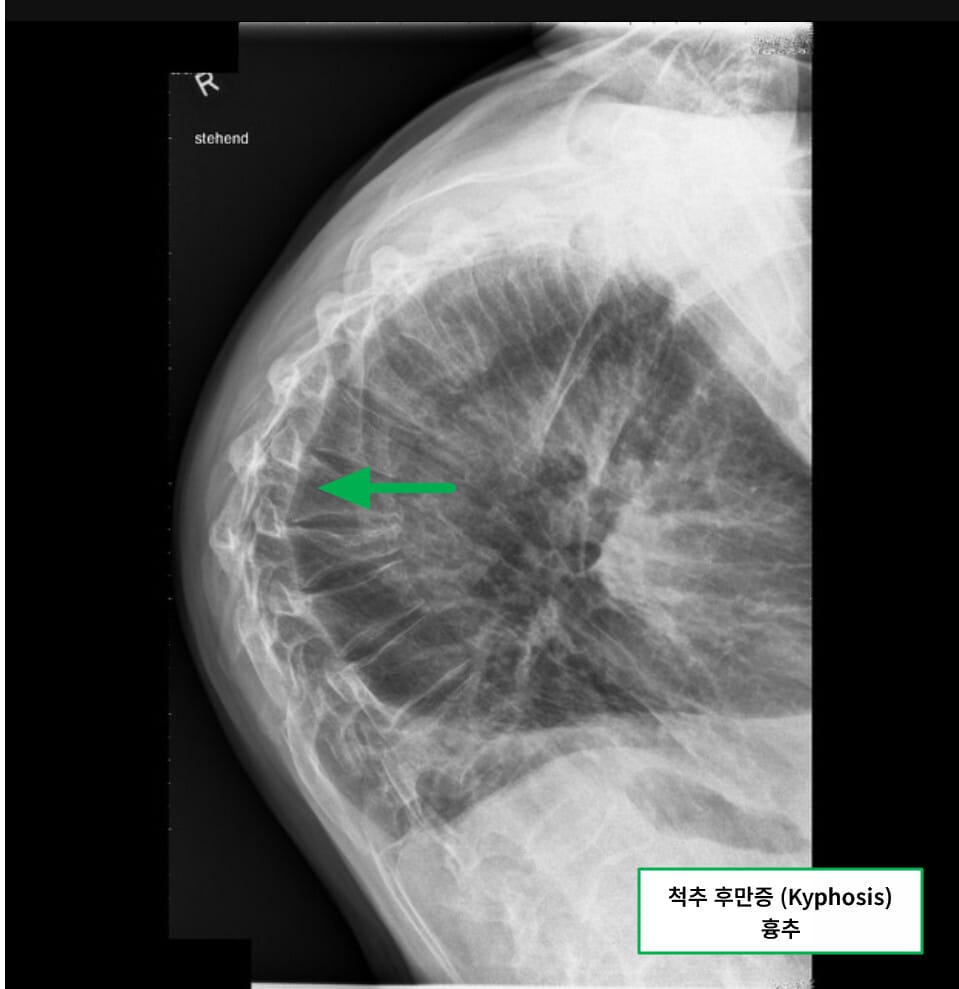

Kyphosis (척추 후만증)

척추 후만증은 척추가 뒤쪽으로 과도하게 굽는 변형으로, 주로 등 부위(흉추)에서 발생합니다.

| 🟧 등이 구부정하게 휘는 현상 |

| 정상 흉추 후만보다 45도 이상이면 후만증으로 간주합니다. |

| 🟧 거북목 또는 꼽추 자세 |

| 심한 경우 몸 전체의 중심이 앞으로 쏠리며 일상 활동에 지장이 생깁니다. |